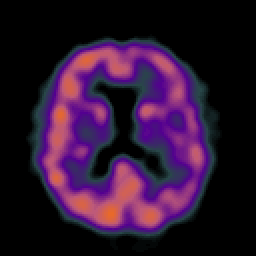

Alzheimer's Disease: SPECT/fMRI overlay -- Slice #6

[Home][Help][Clinical] Slice 6